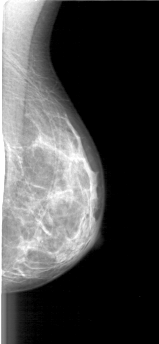

D_4085_1.LEFT_MLO

LEFT_MLO LINES 4816 PIXELS_PER_LINE 2221 BITS_PER_PIXEL 12 RESOLUTION 43.5 NON_OVERLAY